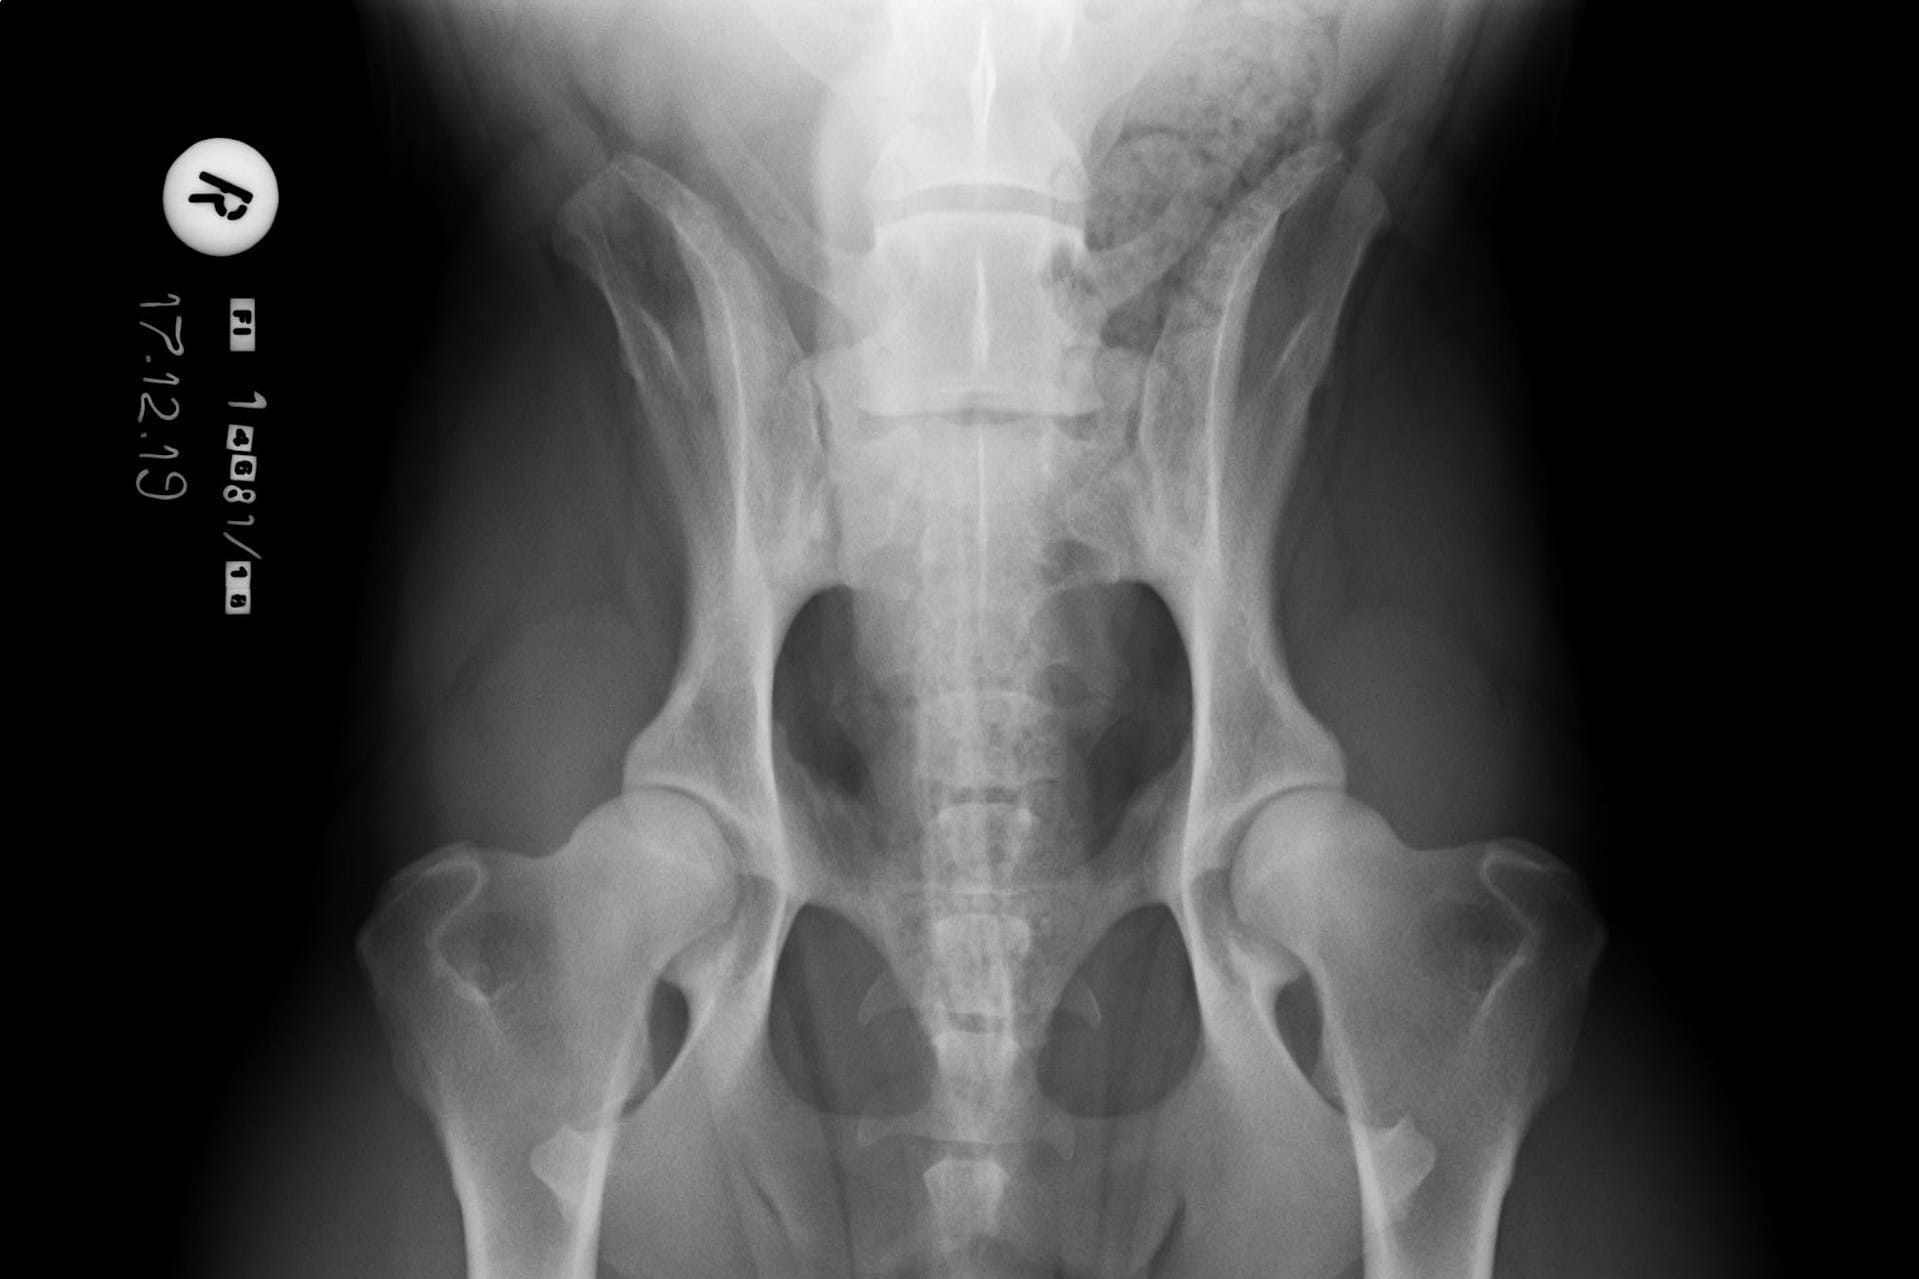

normal spine

A normal canine spine consists of 7 cervical (C1-7), 13 thoracic (T1-13), 7 lumbar (L1-7) and 3 sacral vertebras (S1-3) resulting the total of 30 vertebras. Calculation starts from first thoracic vertebra (T1). The number of caudal vertebras (CD) vary.

Sacrum connects the lumbar spine to pelvis. It’s a part of the pelvis and it lies between the lumbar spine and tail. Sacrum is strong, triangular in shape and it sits between the hip bones. Normal sacrum consists of three fused vertebral segments; S1, S2 and S3.